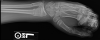

Owwww.Surgury is the answer on this one. Wires need to be added to help re-align the bones.i dont think that will need surgery...but it look painnnnnnnnnnnnnnnful!![]()

Or they might just do what they did to my friend when he broke his wrist.Surgury is the answer on this one. Wires need to be added to help re-align the bones.

Surgury is the answer on this one. Wires need to be added to help re-align the bones.

Put some of those pins that stick outta your wrist while the cast is on, then pull then out when the cast come off for good.

vinay, that would be the best way to go if possible. my dad was a foot and ankle doctor, he says that they can pull those pins right out without the person knowing it. with incredible results